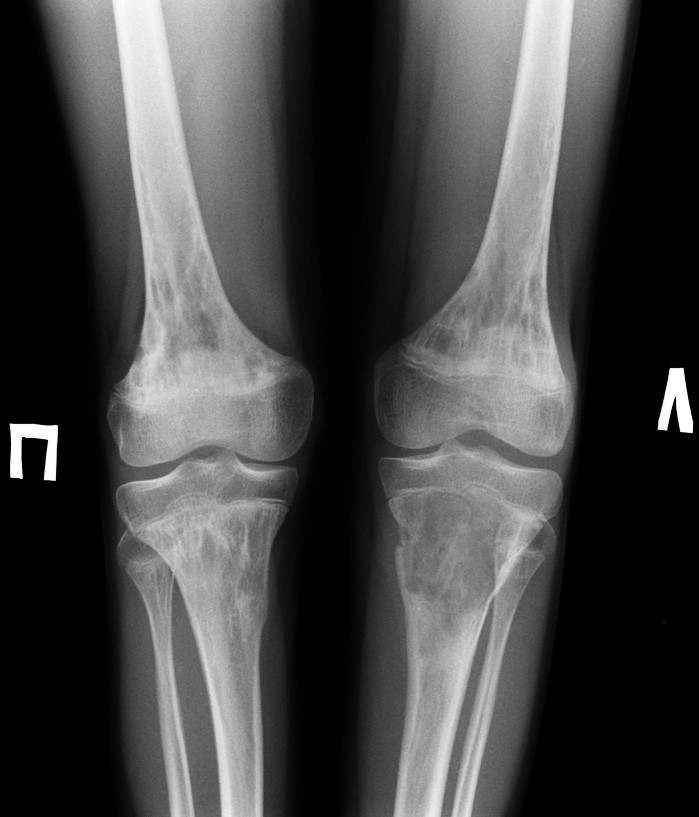

Остеосаркома коленного сустава: информация и поддержка